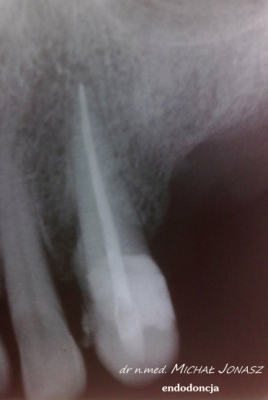

Zmiany okołowierzchołkowe to ogniska zniszczenia kości wokół wierzchołków korzeni zębów. Przewlekłe, nieleczone zmiany zapalne w obrębie korzeni zęba mogą powodować duże uszkodzenia kości i skutkować utratą zębów. Reendo polega na usunięciu materiału, którym wypełnione są kanały i zlokalizowaniu nieprawidłowości, czyli niedostatecznie oczyszczonego lub wypełnionego kanału albo pozostawionego, złamanego narzędzia w jego świetle. Dzięki mikroskopowi problemy anatomiczne, takie jak wąskie, zarośnięte kanały, zakrzywione korzenie, boczne, nietypowe odnogi są możliwe do wyeliminowania.

Diagnostyka obrazowa i wprawne oko Stomatologa są podstawą do podjęcia powtórnego leczenia kanałowego. Wychwycenie zmian patologicznych kierujących na powtórne leczenie kanałowe często jest efektem wnikliwej analizy zdjęć RTG. Powtórnego leczenia kanałowego wymagają zęby, których kanały korzeniowe nie zostały prawidłowo wypełnione. Im dłuższy czas upływa od zakończenia pierwotnego leczenia kanałowego, tym mniejsza szansa, że ząb da o sobie ponownie znać. Nieprawidłowo przeleczony kanałowo ząb, to potencjalnie ogromne ryzyko dla pacjenta. Ząb źle leczony kanałowo przypomina o sobie po wielu latach, bądź w postaci dolegliwości bólowych, bądź przez wolno, bezobjawowo rozwijającą się torbiel. Wytworzenie się torbieli wymaga już interwencji z zakresu chirurgii stomatologicznej. W takiej sytuacji po leczeniu powtórnym pacjent jest kierowany do chirurga na zabieg wyłuszczenia torbieli.

Na zdjęciu RTG efekt leczenia endodontycznego można ocenić po 3 – 6 miesiącach. Każde kanałowe leczenie należy systematycznie kontrolować poprzez wykonywanie rutynowych zdjęć radiologicznych, tak by zawczasu uniknąć nieprzyjemnych problemów.